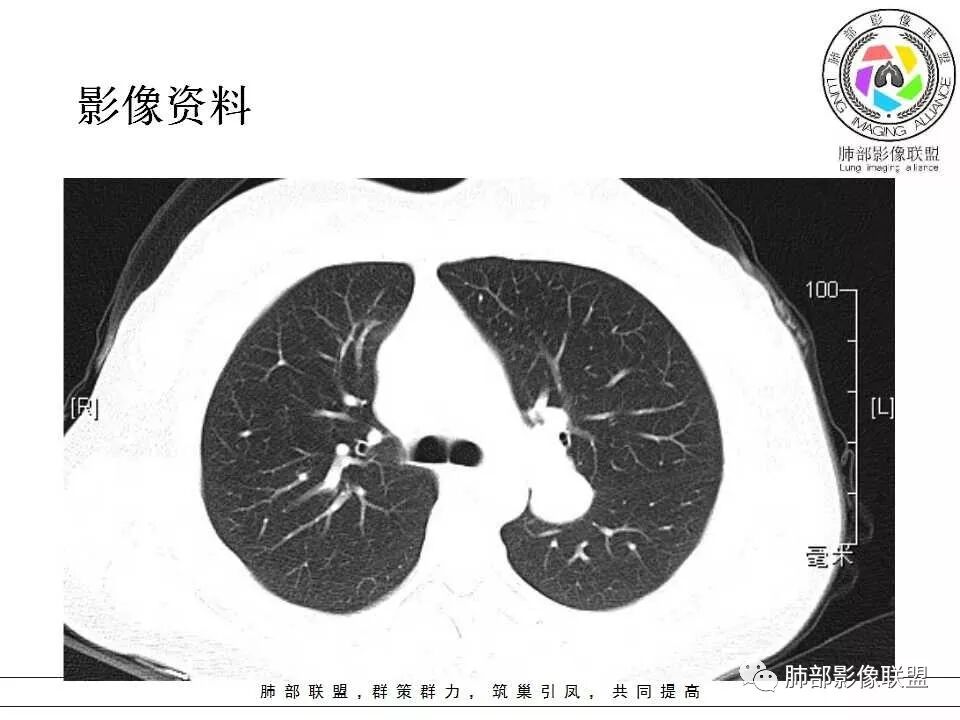

左肺病灶与支气管关系密切,类癌粘膜下生长,支气管略变窄,支气管外病变较大,符合冰山征表现,一年内有增长,考虑类癌,鉴别PSP,建议薄层重建。

我怎么又感觉跨叶间裂了,而且有胸膜尾征和可疑的指状突起,强化很明显,考虑SFT可能大,鉴别类癌和CD

左肺上叶后段紧贴斜裂结节影,支气管通畅,斜裂无移位,说明病灶来源斜裂可能,强化密度均匀,边缘清晰,考虑良性病变,PSP可能性大,鉴别CD。

青年女性,左肺门占位。定位:跨叶间裂,下叶邻近支气管推压,考虑肺外病变。影像表现:血管贴边,边缘光滑,强化均匀,考虑良性病变,PSP可能大,鉴别CD。

青年女性,一年前发现肺结节,复查有增大,未见近期片对比,定位:左肺上叶左肺门旁见实性类圆形结节,边界清晰光整,有部分分叶征,增强有均匀强化,与左上叶后段支气管关系不好判断,左上叶后段支气管未显示,堵塞?狭窄?需冠矢状面看看,定性:常规考虑良性或低度恶性肿瘤,典型的类癌或硬化性肺细胞瘤psp可能,神经源性或神经内分泌肿瘤、巨淋巴结增生症CD不除外,转移瘤、孤立性纤维瘤待排,建议HRCT或支气管镜检查。

年轻女性,左肺门区占位,斜裂推移未跨叶,类圆形,增强扫描明显强化,和支气管关系显示不是太清楚,感觉关系不是太密切,未见阻塞性炎症,一年后有长大,首先考虑PSP,鉴别类癌,SFT。

36岁女性,发现左肺占位1年,时有干咳。CT:左肺门(上叶尖后段?)类圆形结节,边界清,靠前边缘似有GG0,近肺门侧与血管密切接触,似有小凸起,增强见明显均匀强化,似有条片状影往肺门侧血管钻。图片有点少,病灶与支气管的关系看不清(目前的图片与支气管不密切)。随诊结节增大,整体考虑典型类癌可能性大,鉴别硬化性肺细胞瘤。